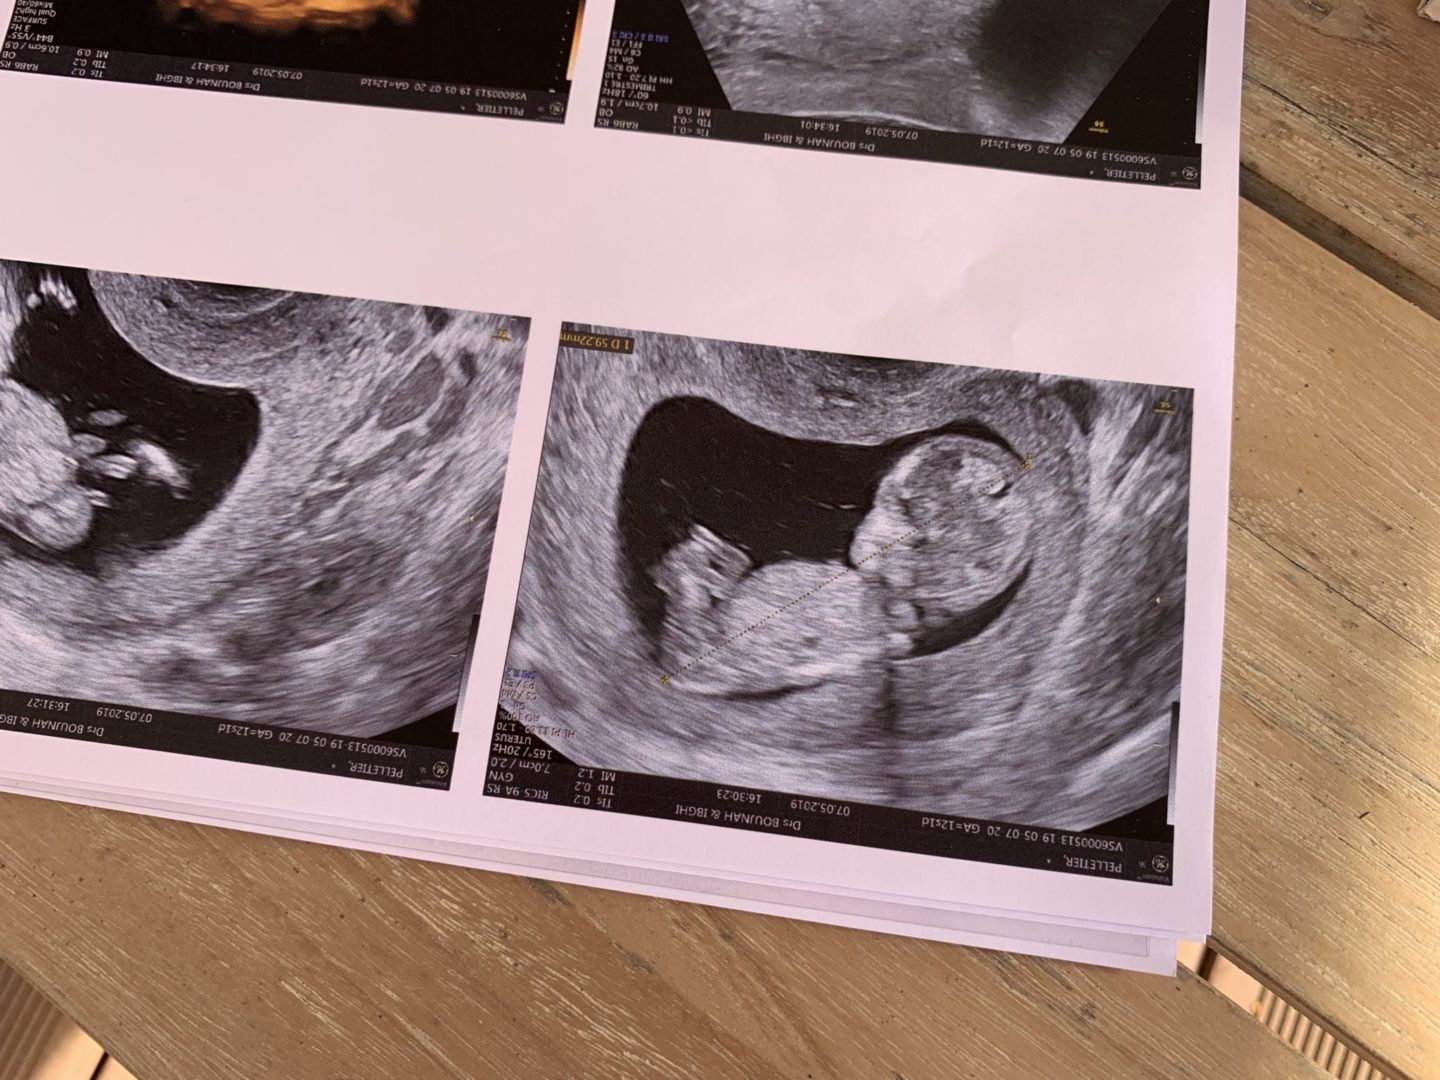

L’écho T1

On est le 7 mai, lendemain de mon anniversaire, et c’est le jour de l’écho T1. On fait ce rendez-vous tous les 3, c’est important pour Louise aussi de voir le bébé de temps en temps, pour rendre la grossesse réelle. La dernière fois qu’on a vu la gynécologue, c’était pour nous dire qu’on était sur une grossesse simple et que le bébé est en bonne santé. C’est un super moment. À ce stade, cela ne se voit pas encore, mais je ressens des gargouillis, des petites bulles. Je n’avais pas du tout ressenti cela pour Louise. Je lui parle. Louise aussi commence à assimiler ce qui se passe, elle lui parle “Coucou le bébé !” et fait des bisous sur mon ventre. Je suis aussi plus sereine et ça se ressent depuis un mois maintenant. Plus de ballonnements, bien moins de tiraillements, juste cette fatigue. Ah oui, j’oubliais, et la poitrine qui me fait très mal aussi ! On arrive à cette écho du 1er trimestre et ça y est, on se retrouve au stade à partir duquel on a commencé le suivi de grossesse pour Louise. C’est d’un coup plus familier, on sait davantage à quoi s’attendre ! On commence l’échographie, et même si on s’en doutait, ce petit bébé commence à bien se former et prendre forme, c’est vraiment fou ! Même si c’est la 2e grossesse, je suis toujours subjuguée face à la nature qui a si bien fait les choses. Le coeur battait très vite, on voyait déjà les détails, ses doigts, ses orteils, c’est fou. Le gynécologue a vu le sexe, mais je préfère attendre un peu que ce soit 100% sûr. On verra la prochaine fois ! J’en profite pour vous remettre la vidéo du rendez-vous que j’ai posté sur Youtube récemment ! Entre Louise qui est surexcitée, Stéphane qui voulait savoir le sexe et moi qui doit les contenir tous les deux, c’est pas une mince affaire !